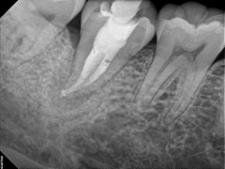

Apexification

In this case, the unhealthy pulp is removed. The MTA will be placed into the apical portion of the root to stimulate hard tissue to form near the root tip (approximately 4-5 mm's of MTA condensed carefully into the apical portion of the root). The coronal portion of the canal space is then filled with restorations to re-enforce the root and provide more structural integrity. The patient is recalled periodically to monitor the progress of the root-end closure, and decide whether other measures, like root end surgery, may be required.